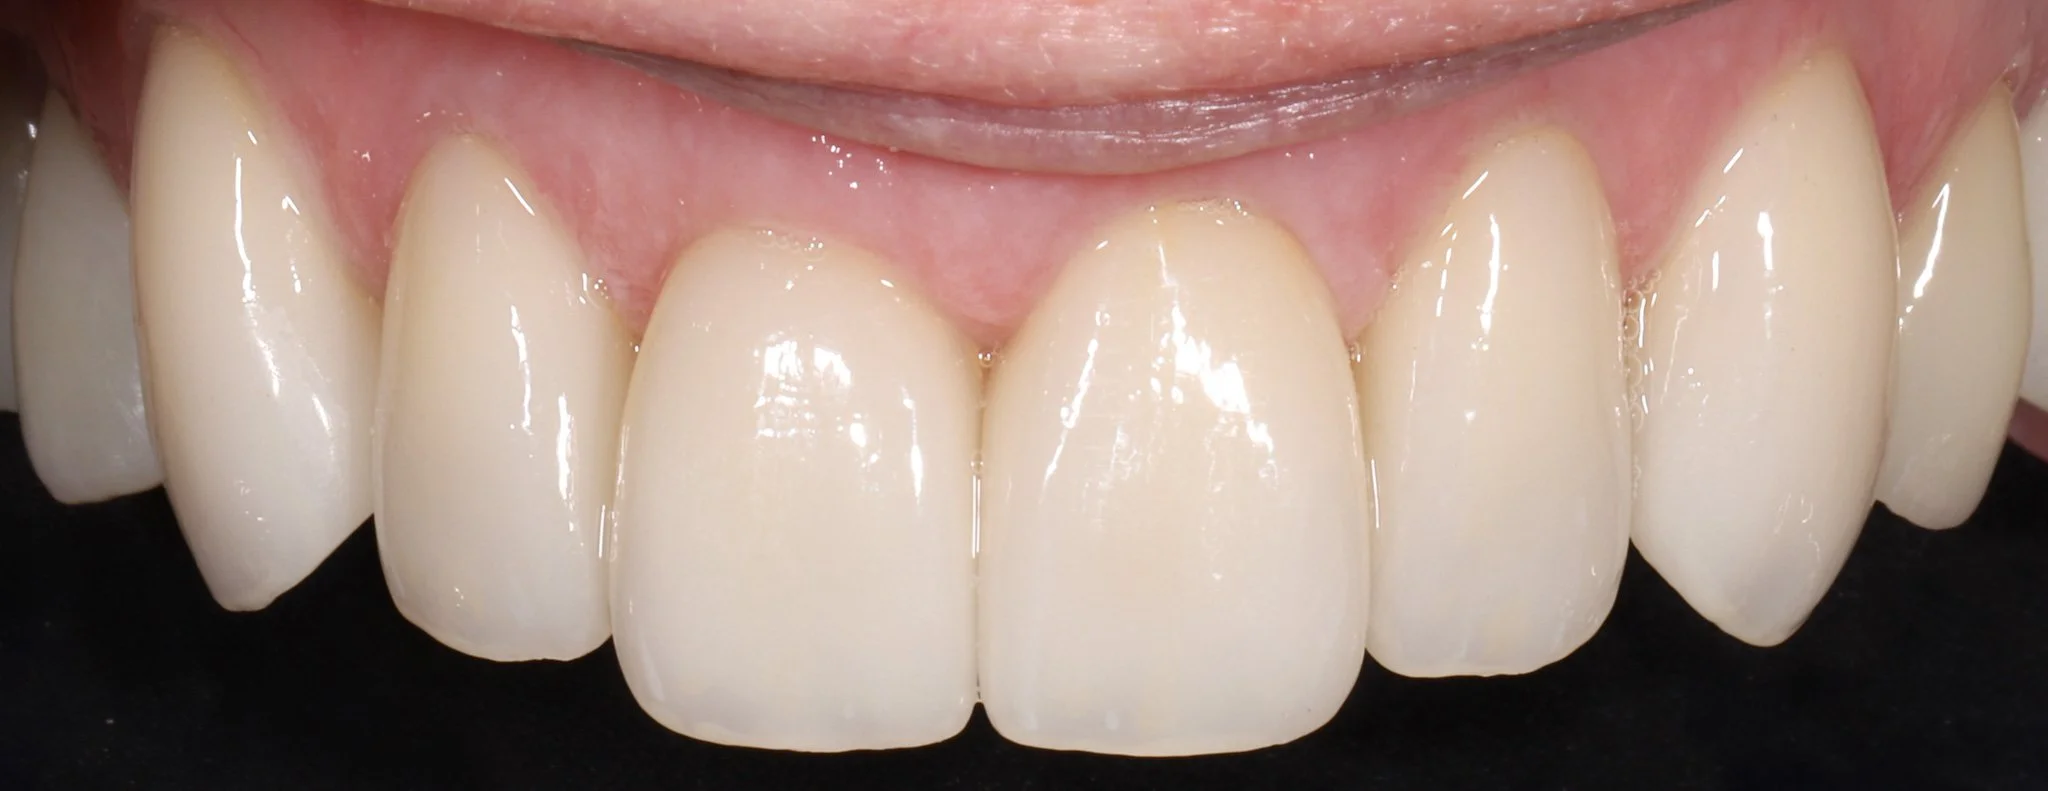

Close-up of a person's upper front teeth, showing straight, white teeth with healthy gums with ideal aesthetics.  These teeth were restored with porcelain crowns.

After: Protected teeth with proper aesthetics and function